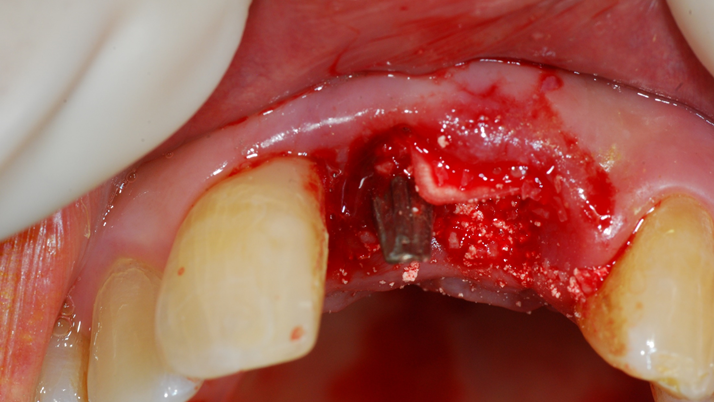

“Achieving a clean surface is the key to treating peri-implantitis!Using a titanium or NiTi brush for the decontamination process along with proper GBR can successfully restore the peri-implant environment. ”

Clinical case: Peri-implantitis treatment case using titanium or NiTi brush

- Courtesy of Dr. Dae-Hee Lee, South Korea -

Dr. Dae-Hee Lee,Maxillary Anterior,Peri-implantitis,Bone regeneration,Aesthetic zone,#21,#22,GBR,Titanium Brush Set